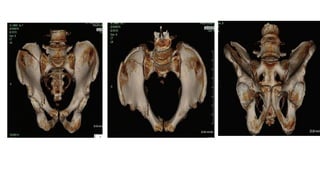

● CT

○ Routine for pelvic ring injury

○ Posterior ring characterization

○ Detailed assessment of fractures

○ Sacral dysmorphisms

● CT ○ Routinefor pelvic ring injury ○ Posterior ring characterization ○ Detailed assessment of fractures ○ Sacral dysmorphisms ● MRI ○ Lumbopelvic dissociation, sacral fractures with neurologic compromise ○ Associated spinal fracture and nerve root compression